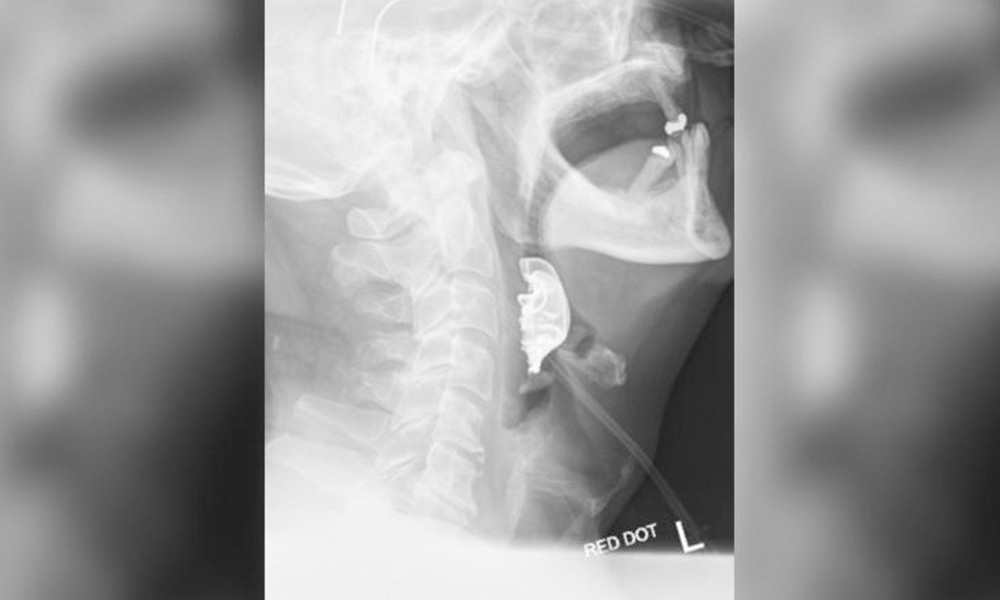

| Phim chụp hàm răng giả mắc trong cổ họng bệnh nhân. |

Cuối cùng, liệu trình chẩn đoán đã xác định được một vật thể hình bán nguyệt nằm chặn ngang dây thanh quản của ông, gây ra các vết xước và sưng tấy trong vòm họng. Người đàn ông đã được đưa vào phẫu thuật khẩn cấp để gỡ bỏ hàm răng giả. Ông đã phải ở lại bệnh viện trong 6 ngày sau đó.